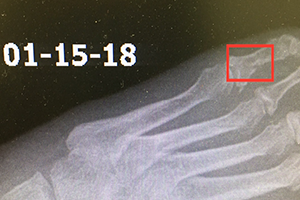

A female patient presented with a broken toe resulting from a slip on the ice December 20th, 2017. This finding was confirmed with x-ray the following morning. She started a regimen with the Wei Fastt patches. Additionally, she started on 1 capsule, 3 times daily of the Wei product Martial. This product helps to activate blood circulation in the bones to expedite the healing process of the Fastt patch. Furthermore she also added in a vitamin product, Intenzyme Forte from Biotics Research Corporation, to help reduce swelling and inflammation. Along with these therapies she increased her calorie and total protein intake to address a nutritional need in her body for further speed in healing.

She continued on a regimen of 5 Fastt patches total, and 2 full bottles of Martial to cover 4 weeks on the protocol. During this time the foot was placed in a boot, with use of a scooter, occasional pressure, and walking on the foot for 2 weeks. After the 2nd week she started to walk more, continuing to keep her foot in the boot as needed. By January 15th, 2018 the patient stated she was not walking with the boot anymore, and had started to wean off it the week prior.